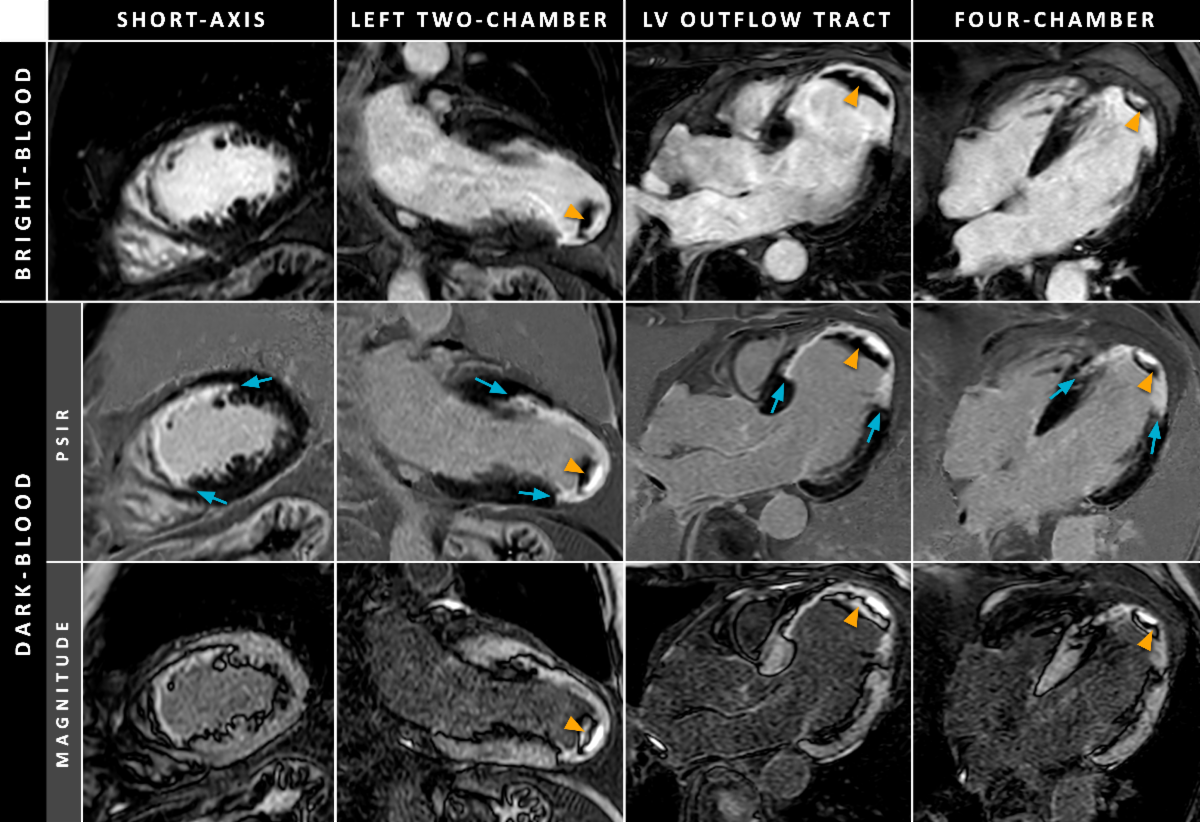

Dark-Blood LGE CMR for Improved Detection of Subendocardial Scar: A Review of Current Techniques

The standard inversion-recovery (IR) sequence with the inversion time (TI) set for myocardium nulling used for LGE imaging has its limitations. Due to the often bright signal of the blood pool, blood may appear equally enhanced as adjacent subendocardial scar regions. During the last 15 years, various novel dark-blood LGE approaches have been proposed to increase scar-to-blood contrast and improve subendocardial scar conspicuity. Most of these methods use additional magnetization preparation mechanisms to either suppress the blood pool signal partly (gray-blood techniques) or null the signal completely (black-blood techniques). These mechanisms include T2 preparation, magnetization transfer, and spin-locking in concert with the standard inversion pulse, and utilization of multiple inversion pulses. Similar effects, however, have also been achieved without using any additional magnetization preparation. As each approach utilizes a different contrast mechanism, a great variety in contrast between the normal myocardium, blood pool, and areas of enhancement can be achieved nowadays. For a mainstream adoption of dark-blood LGE methods, however, clinical availability and ease of use are crucial.

Our latest review article aims to provide a comprehensive overview of the various dark-blood LGE methods. For each method, the employed contrast mechanism and corresponding magnetization preparation scheme are illustrated, followed by a discussion on the findings in phantom, preclinical, and clinical studies. Finally, various aspects relevant for LGE imaging are discussed, conclusions on the current evidence and limitations are drawn, and new avenues for future research are mentioned.

From Holtackers, R.J., et al. (2021). Dark-blood late gadolinium enhancement cardiovascular magnetic resonance for improved detection of subendocardial scar: a review of current techniques. J Cardiovasc Magn Reson, 23(96). https://doi.org/10.1186/s12968-021-00777-6